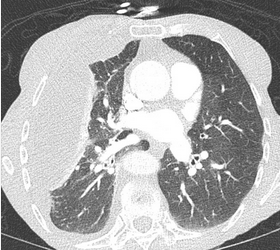

In the emergency department, the patient’s temperature is 38.3 °C; SpO2 is 91% while breathing room air; pulse is 95/min; respirations are 34/min; and BP is 130/85 mm Hg. Physical examination is notable for tachypnea and diminished breath sounds in the right lung field. A chest radiograph is obtained, followed by CT scan of the chest (Figure 1). The patient is placed on high-flow nasal cannula oxygen and admitted to the ICU out of concern for impending respiratory failure. Ultrasonography of the right hemithorax shows a 6-cm area of anechoic fluid above the diaphragm with complex septations. Diagnostic thoracentesis is performed at the bedside and yields 100 mL cloudy fluid. Laboratory values for pleural fluid analysis are shown in Figure 2.